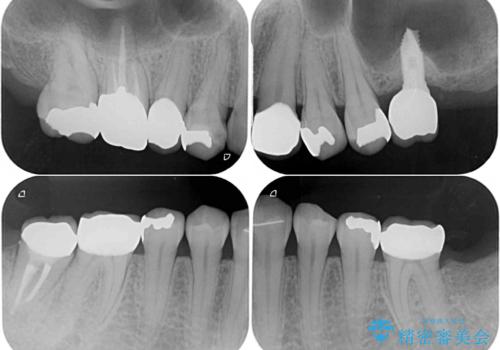

途中通院されなかった時期が何度かあったため、初診から4年以上の年月がかかりましたが、比較的スムーズに治療を進めることができました。

下顎前歯の歯列を整えたことで、上顎前歯の咬み合わせが安定し、自然な口元に仕上げることができました。